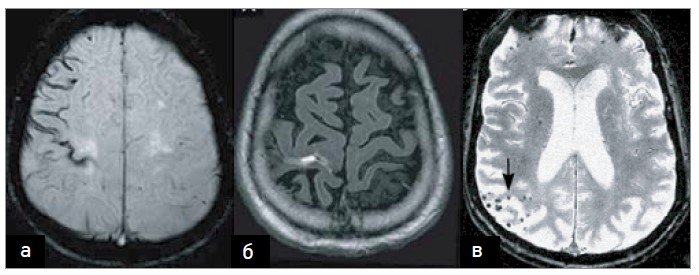

Хвороба Бінсвангера: лікування і його виклики Коли мова йде про хвороба Бінсвангера, лікування стає справжнім викликом для лікарів і пацієнтів.